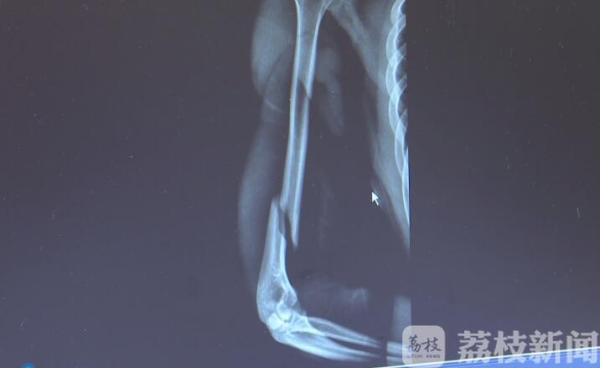

荔枝新闻讯 很多人在较量力气的时候 , 喜欢用扳手腕来分高低 。 近日 , 湖南长沙20岁的小肖在寝室与同学比试扳手腕 , 僵持了40秒左右后 , 他猛然发力想要扳倒对手 , 却听见自己的手臂咔嚓一声 , 断了 。

医生诊断这是一个长的螺旋形骨折 。 意外发生后 , 跟小肖一起扳手腕的小刘一直在医院照顾他 。 小刘是同学们公认的大力士 , 扳手腕那天 , 小刘和小肖一直僵持不下 , 最后小肖突然发力却把自己手给扳断了 。